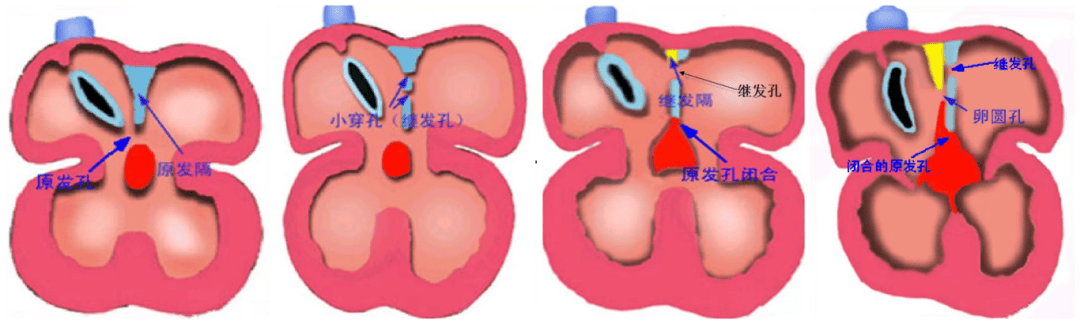

房間隔缺損(Atrial Septal Defect, ASD)是較常見的一種先天性心臟病,由于胚胎期房間隔發(fā)育、吸收或融合異常,導致左右心房之間殘留未閉的房間孔。房間隔缺損可單獨存在,或與其他心血管畸形合并存在。

房間隔缺損是由原發(fā)隔和繼發(fā)隔組成,原發(fā)隔位于左側(cè),繼發(fā)隔位于右側(cè)。

房間隔缺損分原發(fā)孔型與繼發(fā)孔型,通常房缺是指繼發(fā)孔型。根據(jù)缺損部位不同分為四型:

中央型又稱卵圓窩型:位于房間隔中部相當于卵圓窩部位,此型最常見,76%;

下腔型:缺損位于房間隔后下方,與下腔靜脈入口相延續(xù),12%;

上腔型:位于房間隔后上方,缺損與上腔靜脈入口無明確界限,3.5%;

混合型:兼有上述兩種以上的巨大房間隔缺損,8.5%。